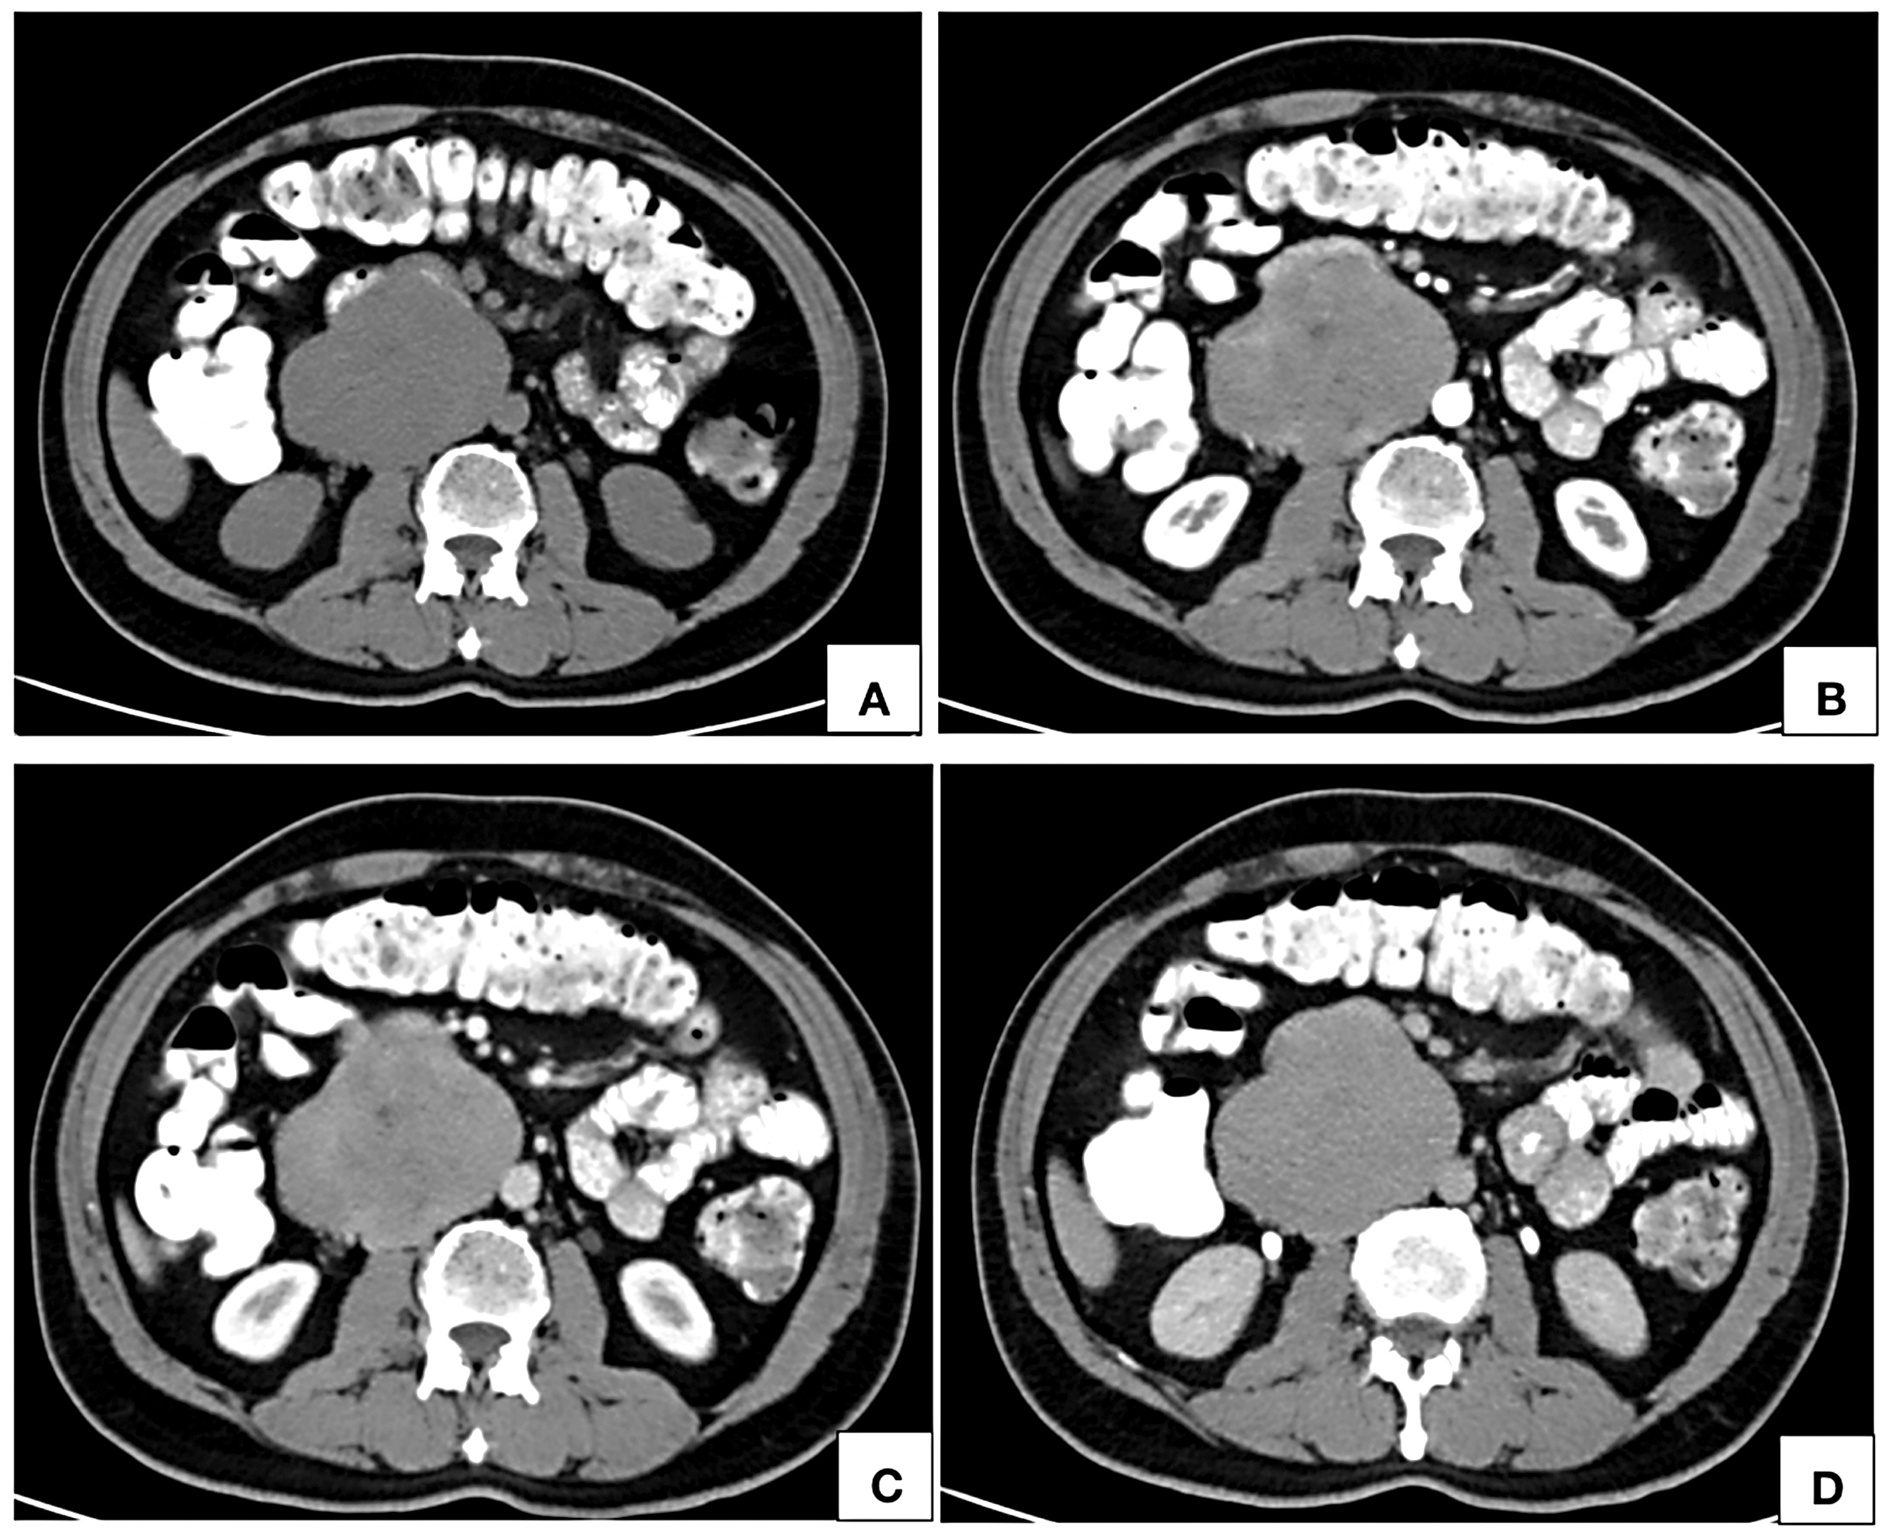

Routine ultrasonographic examination revealed a circumscribed hypoechoic lesion in the upper abdomen measuring 6.6 × 6.3 × 5.9 cm (CC × AP × Tr). For further evaluation, patient underwent computed tomography which revealed a circumscribed retroperitoneal soft tissue lesion in right side of midline, measuring 7.3 × 7.5 × 8.1cm (CC × AP × Tr). The lesion showed inhomogeneous contrast uptake on arterial phase and homogeneous enhancement on portal venous and delayed phases with few nonenhancing areas within. It was abutting the inferior vena cava posteriorly with imperceptible

lumen at the site of maximum contact. However, proximal and distal segments of the inferior vena cava showed normal contrast opacification. Medially, the lesion was in relation to the abdominal aorta. Second and third part of duodenum and head of pancreas were displaced anterosuperiorly. Magnetic resonance imaging (MRI) showed a homogeneously enhancing circumscribed lesion in the retroperitoneum on right side of midline appearing isointense on T1W, hyperintense on T2W showing restricted diffusion. Few cystic areas were seen within the lesion. On prone imaging, the lumen of inferior vena cava was still imperceptible at the site of maximum contact. No obvious intraluminal extension was seen. Whole body positron emission tomography CT revealed mild FDG uptake with a maximum standard uptake value (SUVmax) of 4.1. No distant metastases were found.

These tumors commonly show heterogeneous enhancement with areas of necrosis within [9, 14, 15]. Sessa B et al [10] reported inhomogeneous early enhancement followed by homogenous filling in portal venous phase. We observed inhomogeneous contrast uptake in arterial phase followed by near homogeneous enhancement in portal venous and delayed phases with nonenhancing areas within. Few authors have also reported presence of calcification [16, 25] and hemorrhage [26] within the lesion.